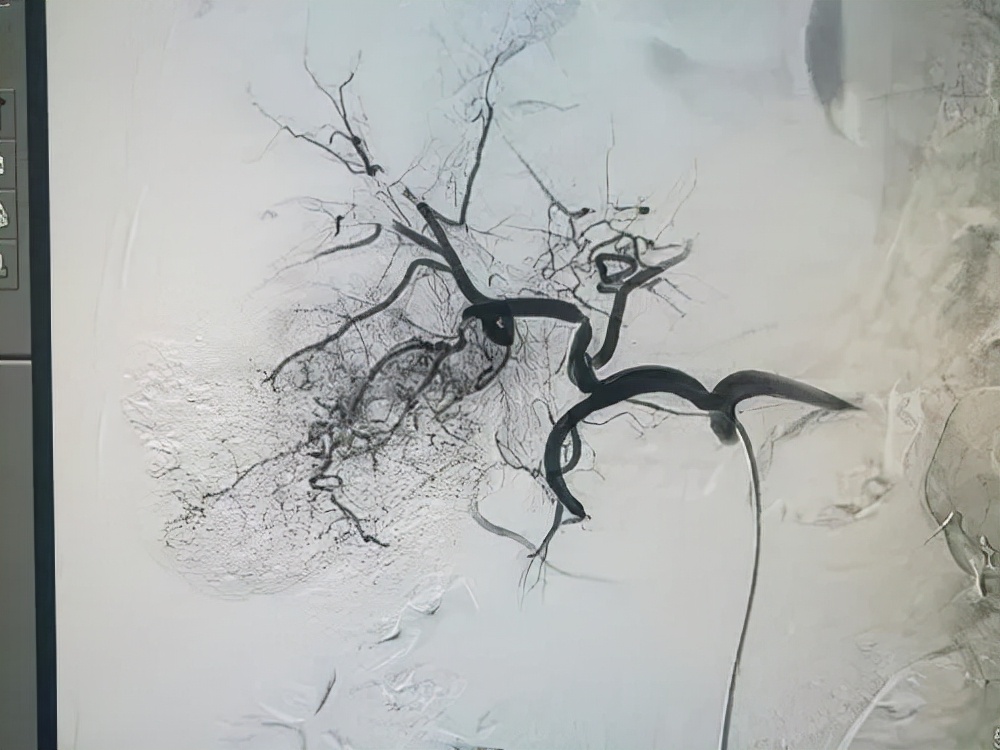

胡女士,女,70岁,曾于2019年12月1日,胡女士因上腹出现无明显诱因疼痛,后前往医院检查,在行胸部CT检查提示肝左叶肿块;2019年12月4日行上腹部磁共振检查提示:(1)肝左叶外侧段结节,考虑肿瘤性病变可能;(2)左侧肝内胆管扩张。肿瘤标记物:甲胎蛋白2.54ng/mL,糖类抗原测定CA19-9值18309U/mL。诊断为:肝左叶肝癌。2019年12月14日行肝癌栓塞+灌注化疗术,术后予以保肝、抗癌、抗感染、增强免疫等对症治疗后出院。

然而一周之后,胡女士便再次出现上腹疼痛,且伴有食欲不振,乏力,急躁等症状。在经过对症治疗没有明显缓解之后,胡女士决定行中医治疗,遂到乐启生门诊进行就诊。